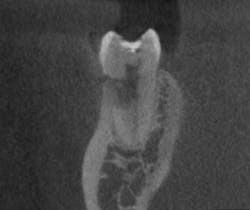

Top clinical articles

Top endodontics articles